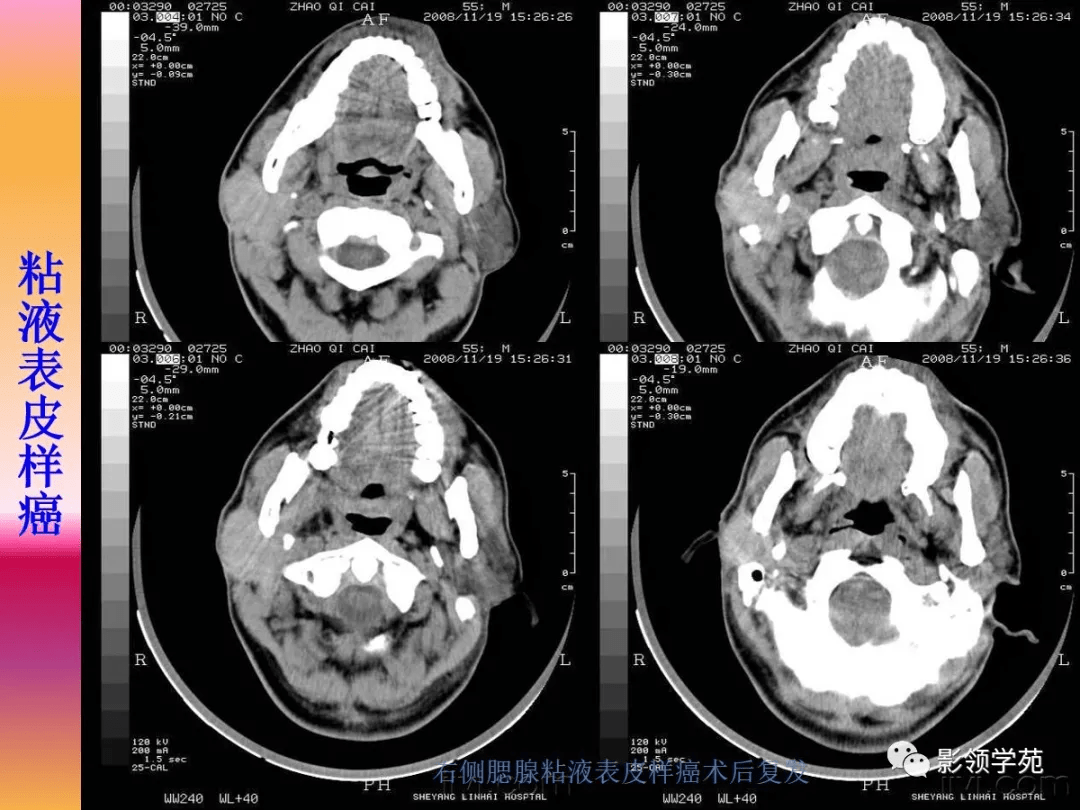

腮腺疾病的ct诊断与鉴别诊断

图片尺寸846x636